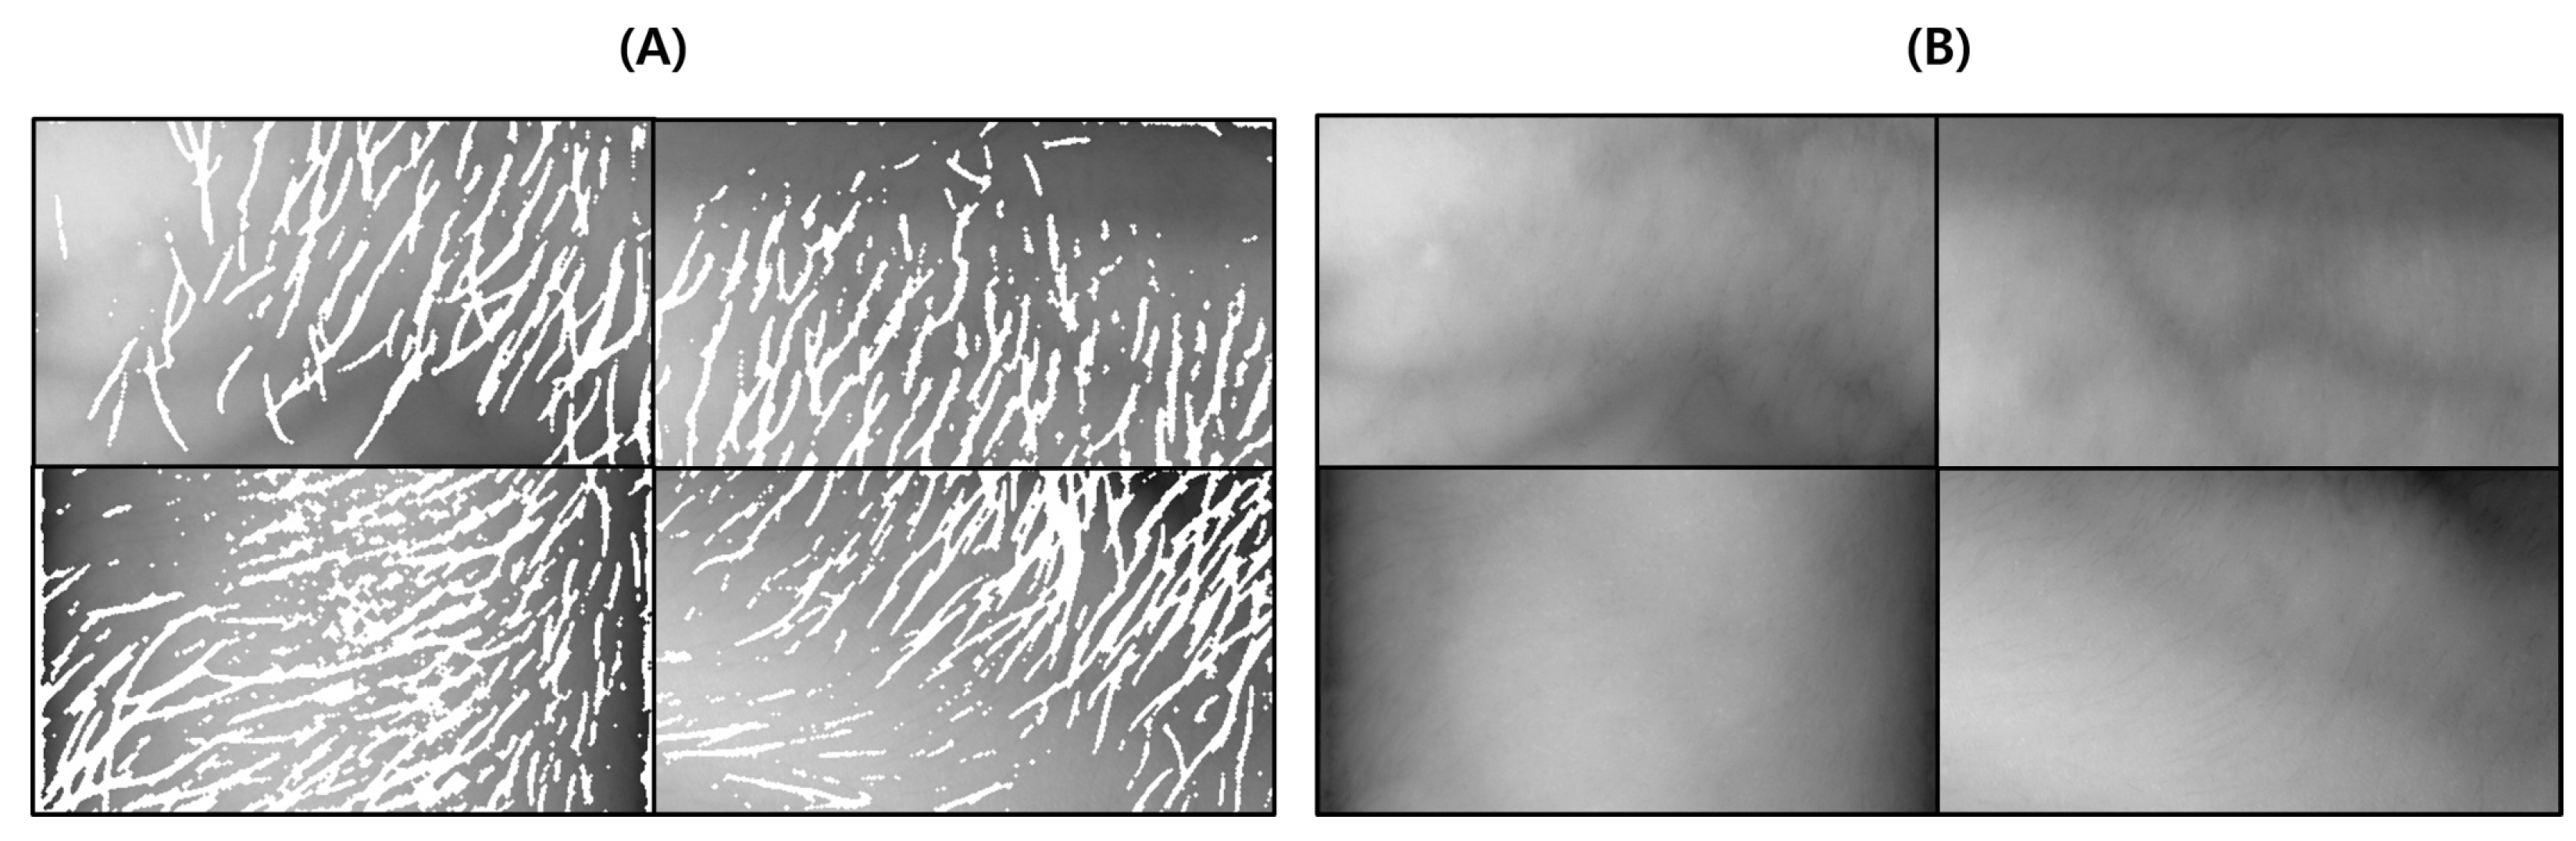

This test was conducted to determine the degree to which the proposed body hair noise removal algorithm improves the performance of the vein image processing algorithm. Based on the original image including body hair noise, Figure 15D was obtained, and the performance of the proposed algorithm was verified with a total of 10 images.

Figure 15.

Image operation results with body hair noise: (A) is a test image created for algorithm verification, and (B) is an artificial blood vessel layer used to create the image. (C) is the resultant image of the proposed algorithm including the hair noise removal function, and (D) is the resultant image of the Veinvu-100 algorithm.

As a result of the test, it was possible to extract a clearer and more distinct vein path than with the vein image processing algorithm installed in Veinvu-100, and the results are shown in Figure 16. Figure 16 was constructed by randomly selecting three images from among the images used in this verification.

Figure 16.

Result of applying SSIM to the results of the proposed algorithm and Veinvu-100 algorithm: (A,B) are binary images obtained by applying the proposed and Veinvu-100 algorithms, respectively, and (C,D) are the results of comparing (A,B) with the vascular layer using SSIM.

As can be seen in Figure 16, in (C) overall, compared to (D), the effect of body hair noise was reduced, the contrast of blood vessels was clearer, and the cutoff or omission of blood vessels was reduced. This can be seen from the histogram of (C). In the case of (C), components other than blood vessels are removed to maximize contrast with blood vessels. A histogram distribution similar to image (B), including only the blood vessel layer, can be confirmed. On the other hand, in (D), the contrast of body hair is the strongest. As a result, the visibility of blood vessels with relatively weak contrast is somewhat less improved. It can be seen that the histogram distribution is also similar to the original image.

For objective performance verification between the proposed and Veinvu-100 algorithms, SSIM-based similarity evaluation was performed using the output images of each algorithm.

In Figure 16C, compared to (D), it can be confirmed that the overall noise was sufficiently reduced to be clearly identified with the naked eye. As a result of checking the similarity for all 10 images used in the test, the proposed algorithm measured an average SSIM of 74.93%, and the VeinVu-100 algorithm had an average of 64.55%, indicating that the proposed algorithm improved performance by 10.38% compared to VeinVu-100. Detailed verification results can be seen in Figure 17 and Table 3 below.